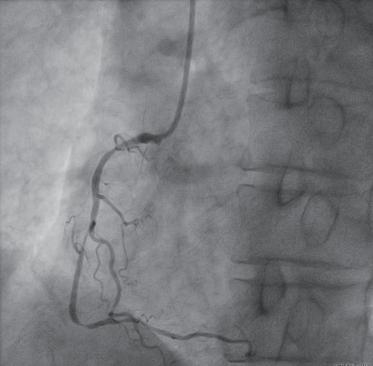

(1)行常规经桡动脉穿刺冠状动脉造影(图1-2-1),以查看血管情况。

图1-2-1 右冠状动脉狭窄造影